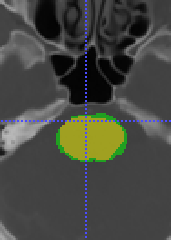

To model , we propose using a half-Gaussian distribution based on nodule size distribution because is correct if it is within the nodule area (center slice of as , and nodule size can be empirically estimated based on existing data) for nodule detection in Fig. 17(a). For lung lobe prediction , a logistic regression model is used based on relative value of nodule center after lung segmentation. That is

| (22) |

where is the associated weights with lobe location for logistic regression, feature , and is the total size of image after lung segmentation. In the experiments, we found the logistic regression converges quickly and is stable.